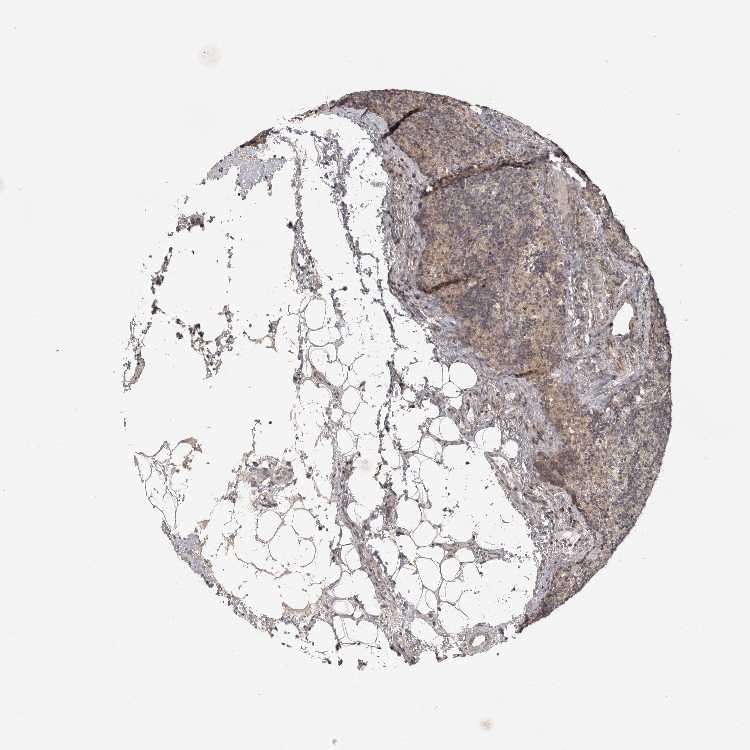

LYMPH NODE - Antibody stainingi

Antibody staining in the annotated cell types in the current human tissue is reported as not detected, low, medium, or high, based on conventional immunohistochemistry profiling in selected tissues. This score is based on the combination of the staining intensity and fraction of stained cells.

Each image is clickable and will lead to virtual microscopy that enables deeper exploration of all samples and also displays staining intensity scores, fraction scores and subcellular localization as well as patient and tissue information for each sample.

Antibody HPA027468Antibody HPA028668

Germinal center cells Not detectedNot detected

Non-germinal center cells LowNot detected

Information about each individual sample is listed below, including gender, age, a tissue section image and estimated fractions of cell types. nTPM (normalized transcripts per million) values give a quantification of the gene abundance which is comparable between different genes and samples.